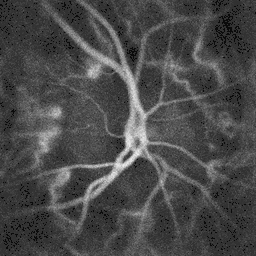

![]() Ophthalmoscopy photograph showing the optic disc as a bright area on the right where blood vessels converge. | |

The ganglion cell axons form the optic nerve after they leave the eye. The optic disc represents the beginning of the optic nerve and is the point where the axons of retinal ganglion cells come together. The optic disc in a normal human eye carries 1–1.2 million afferent nerve fibers from the eye toward the brain. The optic disc is also the entry point for the major arteries that supply the retina with blood, and the exit point for the veins from the retina.[1]

The optic disc is located 3 to 4 mm to the nasal side of the fovea. It is a vertical oval, with average dimensions of 1.76mm horizontally by 1.92mm vertically.[2] There is a central depression, of variable size, called the optic cup. This depression can be a variety of shapes from a shallow indentation to a bean pot—this shape can be significant for diagnosis of some retinal diseases.

Almost all eye structures can be examined with appropriate optical equipment and lenses. Using a modern direct ophthalmoscope gives a view of the optic disc using the principle of reversibility of light. A slit lamp biomicroscopic examination along with an appropriate aspheric focusing lens (+66D, +78D or +90D) is required for a detailed stereoscopic view of the optic disc and structures inside the eye.

A biomicroscopic exam can indicate the health of the optic nerve. In particular, the eye care physician notes the colour, cupping size (as a cup-to-disc ratio), sharpness of edge, swelling, hemorrhages, notching in the optic disc and any other unusual anomalies. It is useful for finding evidence corroborating the diagnosis of glaucoma and other optic neuropathies, optic neuritis, anterior ischemic optic neuropathy or papilledema (i.e. optic disc swelling produced by raised intracranial pressure), and optic disc drusen.